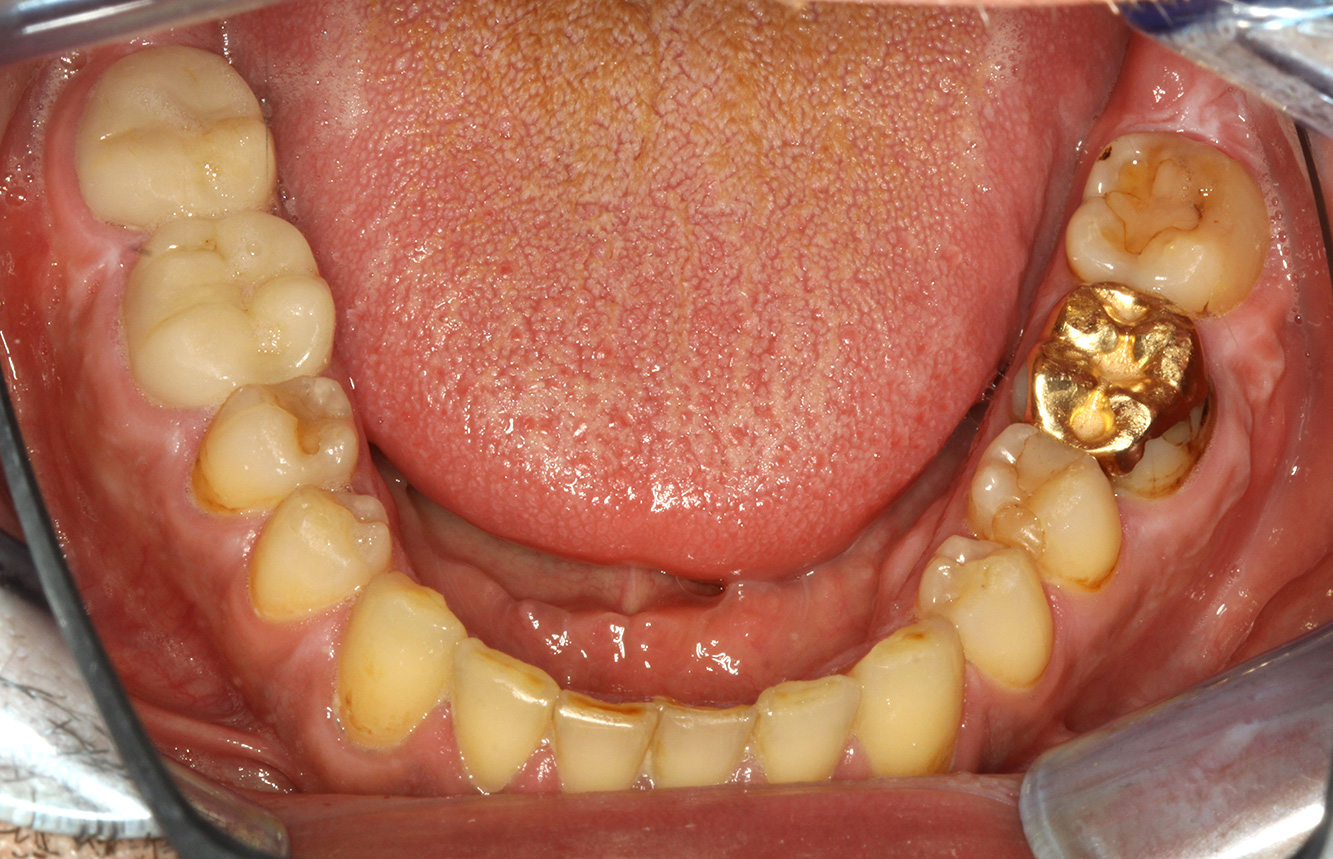

A 71-year old patient presents with having previously undergone a kidney transplant and with a history of hypertonia (high blood pressure). Due to his medical history, long-term medication with cyclosporine is required to suppress the immune system, as well as amlodipine to lower blood pressure. The patient also reports sensitive and bleeding gums. From an oral health perspective, the patient has undergone dental restoration and has eight missing teeth, pronounced gingival growth, and grade B, stage II periodontitis with active pockets and initial root caries on tooth 22. The caries risk assessment determines a moderate risk of caries (API 60). The following treatment recommendations can be determined for the prophylaxis session. more